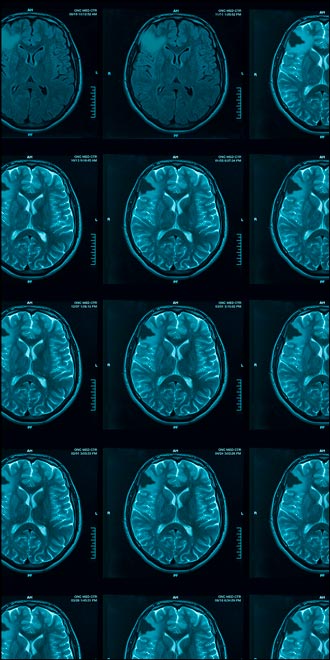

VORANIGO (40 mg tablets) is a prescription medicine used to treat adults and children 12 years of age and older with certain types of brain tumors called astrocytoma or oligodendroglioma with an isocitrate dehydrogenase-1 (IDH1) or isocitrate dehydrogenase-2 (IDH2) mutation, following surgery. Your healthcare provider will perform a test to make sure that VORANIGO is right for you. It is not known if VORANIGO is safe and effective in children under 12 years of age.